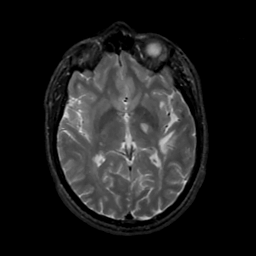

MR Study #4, March 3, 1991 -- Slice #25

[Home][Help][Clinical][Tour 1][Tour 2] Slice 25